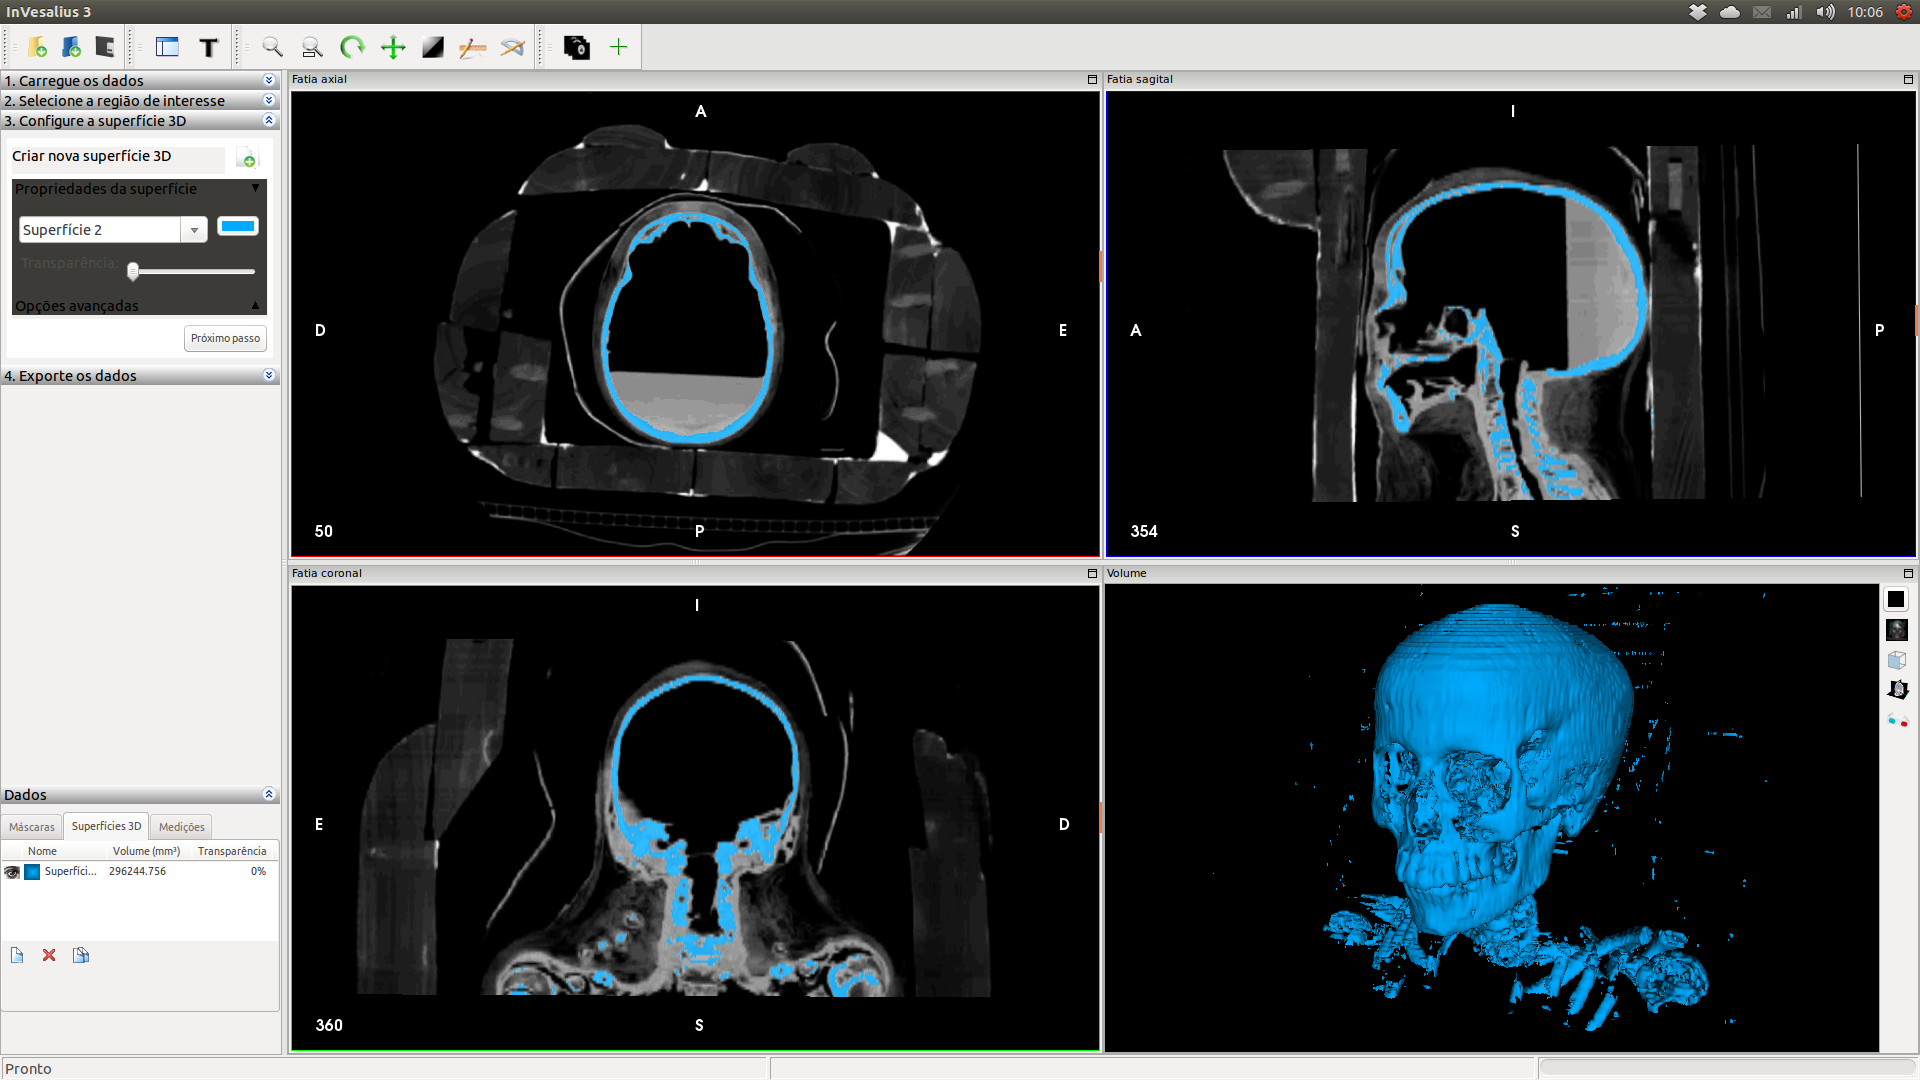

Ao se filtrar os dados no InVesaius, ocultando a faixa correspondente a madeira, eis que o esqueleto lá dentro se revelou em 3 dimensões. As “impurezas” em volta do ataúde ao que parece trata-se do material de vedação entre uma madeira e outra.

Para estimar a idade, uma das formas mais acessíveis é analisar os dentes. O problema é que filtrar a área dos ossos se tornaria um trabalho infindável, posto que o material de vedação seria exportado juntamente com o crânio. Felizmente o InVesalius conta com uma ferramenta de seleção e exclusão de áreas, que acabou ajudando bastante na filtragem dos ossos, deixando praticamente apenas o crânio para exportação.